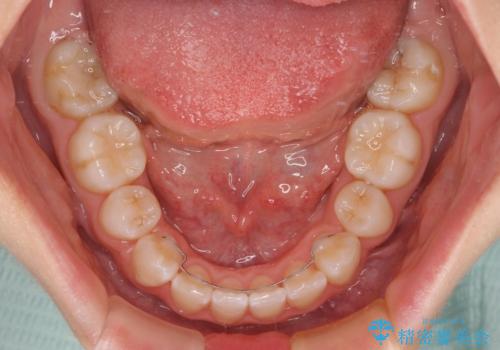

- クリアブラケット

- 1年6ヶ月

- 前歯の出っ歯と口元の閉じにくさを気にして来院された患者様です。

口元を積極的に引っ込めるために、上下左右の小臼歯4本を抜歯することとしました。

4本の歯を抜歯したことで、飛び出していた口元が引っ込み、横顔が大きく改善されました。